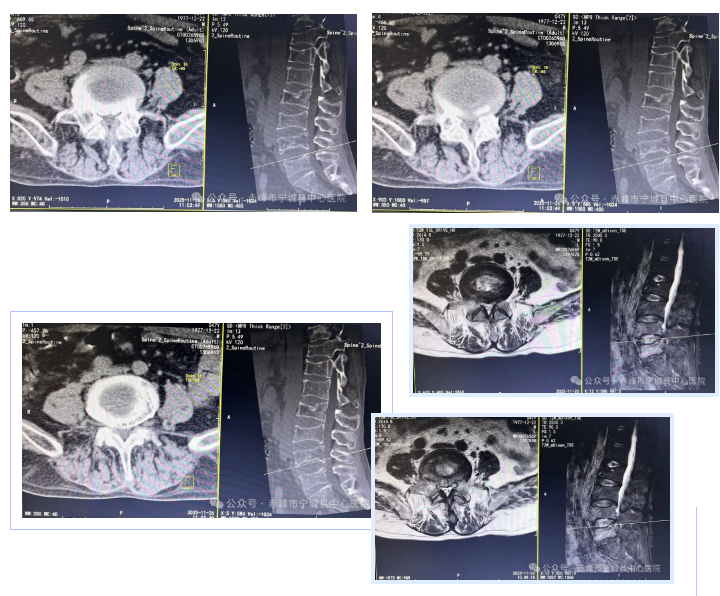

二:腰椎椎管狭窄症

术后影像